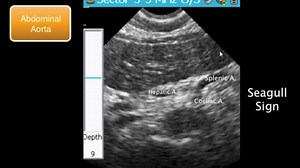

Abdominal Aorta Model Labeled 的热门建议 |